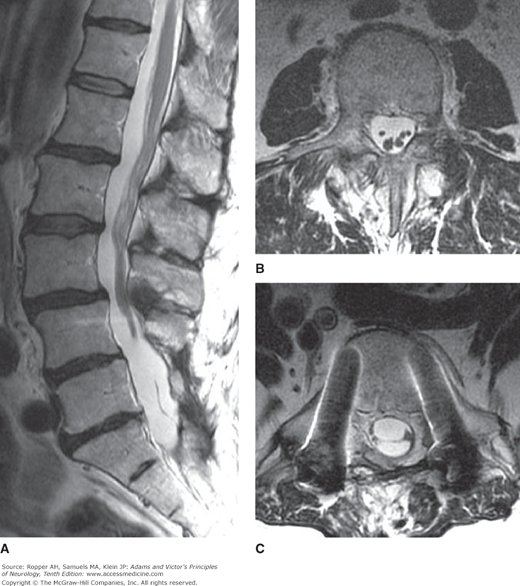

Lumbosacral MRI of a Patient With Lymphoma

Lumbosacral MRI of a patient with lymphoma, with radiation-induced arachnoiditis causing severe back pain and leg weakness. A. Sagittal T2-weighted MRI showing clumping of the nerve roots of the cauda equina. B. Axial T2-weighted image at the L3 vertebral level showing clumping of the nerve roots. C. Axial T2-weighted image at the L5 vertebral level showing lateral displacement of nerve roots by acquired arachnoid cysts. There are bilateral metallic pedicle screws.